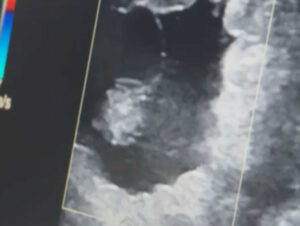

コラム・エッセイ ブログ・手記 [連載・片目のサラブレッド福ちゃんのPERFECT DAYS]僕たちが手がけているのは命のある生き物(シーズン1-37) 2025年3月11日 川崎競馬のパドック解説を終え、入場門の外に出ると、僕は真っ先に慈さんに電話をかけました。もう遅い時間だから寝ているかもと心配しましたが、慈さんは日高の生産者たちとの飲み会がちょうど終わったところだったようで、あっさりと電話に出てくれました。 「スパツィアーレの23のレポジトリの結果が今日出ましたので」と慈さんが切り出し... 治郎丸敬之